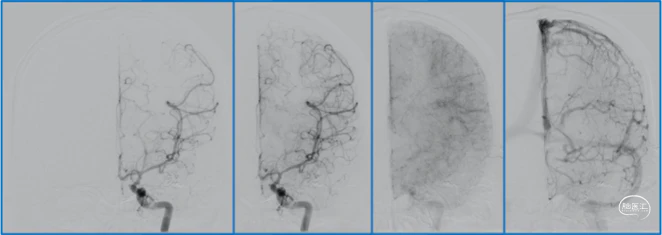

典型病例

![]()

蝶顶窦旁DAVF,可吸引前和中颅窝硬膜的所有动脉参与供血。其中颈内动脉及其分支的供血可以使用显微外科技术阻断;颈外动脉的供血动脉可以使用介入栓塞技术阻断。

介入栓塞眼动脉供血的要点:超选左侧眼动脉,跃过视网膜中央动脉,栓塞脑膜回返动脉对DAVF的供血。目的:保护眼动脉视网膜中央动脉分支,避免后期栓塞颈外动脉的供血动脉时损伤眼动脉。

稳妥的外科治疗方案:先介入栓塞颈外动脉的供血动脉,然后显微手术切断颈内动脉的供血动脉,阻断引流静脉,电凝封闭硬膜瘘口。